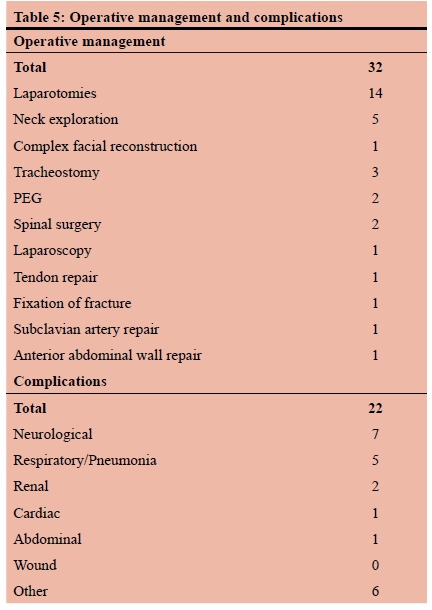

RESULTS: During the five-year study period, a total of 179 patients were included. The mean age was 29 years (SD12) and there were 139 (77%) males and 40 (23%) females. Of these, 16 had a previously established psychiatric diagnosis and two had a prior history of having sustained self-harm. The previously diagnosed psychiatric illnesses included mood dysphoria disorders (5), schizophrenia (3), substance abuse and dependency (1), anti-social personality disorder (1) and unspecified (6). The mechanism was penetrating trauma in 47 (26%). The penetrating mechanisms included stab wounds (SW) in 33, gunshot wounds (GSW) in 10, broken glass in 2 and a single impalement. Blunt mechanisms accounted for the remaining 131 (73%) injuries. The most common mechanism of blunt self-harm was hanging in 101 patients. This was followed by vehicular related trauma (8), jumping in front of a train (1) and jumping from a height (1). In 17 patients the exact mechanism of the blunt trauma was unclear. There was no statistical difference in the mechanism of injury between male and female patients. There were 38 (28%) men and 9 (23%) women who sustained a penetrating injury and there were 100 (72%) male and 31 (78%) female patients who had a blunt mechanism of injury. A total of 53 CT scans were obtained, 40 chest X-rays, 9 abdominal X-rays and 2 ultrasounds. There were 113 neck injuries, 68 head injuries, 24 abdominal injuries, 15 upper limb and 15 lower limb injuries and four facial injuries. A total of 32 operations were performed. These included laparotomy (14), neck exploration (5), tracheostomy (4). A total of 22 patients developed a complication

A total of 53 CT scans were obtained, 40 chest X-rays, 9 abdominal X-rays and 2 ultrasounds. Table 4 tabulates these investigations. There were 113 neck injuries, 68 head injuries, 24 abdominal injuries, 15 upper limb and 15 lower limb injuries and four facial injuries. A total of 32 operations were performed. These included laparotomy (14), neck exploration (5), and tracheostomy (4). The remainder are listed in Table 5. A total of 22 patients developed a complication. These are broken down in Table 5. A total of 4.5% of patients required ICU admission and the overall mortality rate was 2.5%. Figure 1 demonstrates a self-inflicted laceration of the neck in an acutely psychotic patient. This required a neck exploration and ligation of a severed internal jugular vein and reconstruction of the injured larynx. Figure 2 is the CT scan of a man who shot himself in the face. He survived the injury and required extensive reconstructive surgery.